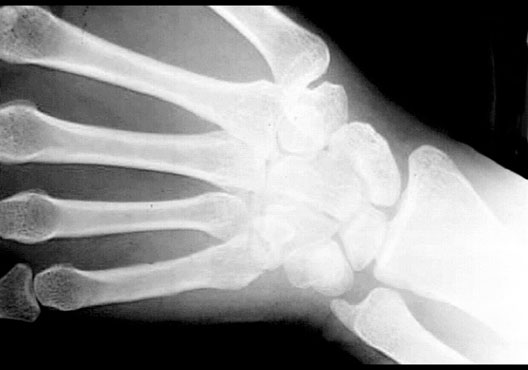

Wrist Bones

Roll mouse over image to display labels.

1. Trapezoid bone

2. Trapezium bone

3. Capitate bone

4. Scaphoid bone

5. Lunate bone

6. Hook of the Hamate bone

7. Hamate bone

8. Triquetral bone

9. Pisiform bone